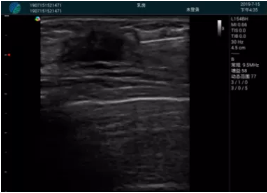

清晰顯示腺體內(nèi)低回聲快影,邊界清晰,包膜較光滑

確定進針路徑并實時監(jiān)測抽吸針與腫塊位置關系

抽吸針進入腫塊內(nèi)部進行旋切

抽吸過程中可見腫塊明顯縮小,并根據(jù)腫塊位置改變針道位置

抽吸旋切后再進行超聲復查,原腫塊區(qū)域未見殘留組織及出血